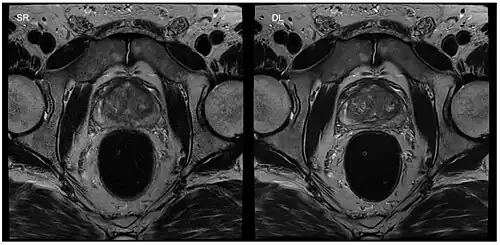

Applications in interventional MRI, which refers to the monitoring of minimally invasive surgical procedures, are possible by interactively changing parameters such as image position and orientation. This application is particularly helpful when a 3D image of the tissue is needed during surgery.[11] It requires an in-room display for the physician to use during the procedure as well as the use of MRI-safe surgical tools. These include ceramic, plastic, or titanium, which is a paramagnetic metal. By using bSSFP and parallel imaging with multiple coils, frame rates of 5-10 frames per second have been accomplished, allowing for the visualization of cardiac procedures.[11]